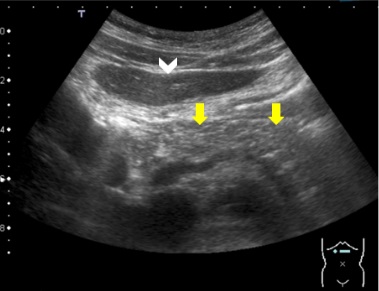

Está en seguimiento por esteatosis y obesidad conjuntamente en Digestivo y Endocrinología Pediátrica. A la edad de 14 años se observa una mejoría en el índice de masa corporal y resolución de la esteatosis hepática, persistiendo la alteración a nivel pancreático (Fig. 1). Analítica dentro de la normalidad en todo momento, incluidas enzimas hepáticas, enzimas pancreáticas, glucemias seriadas e insulinemia. Es dado de alta por buena evolución ecográfica y ausencia de síntomas, para continuar el seguimiento desde Atención Primaria.

| Figura 1. Ecografía abdominal. Corte transversal de la región epigástrica. Se aprecia hiperecogenicidad difusa del parénquima pancreático (flechas amarillas) con respecto al parénquima hepático (rotulado como una cabeza de flecha) |

Para establecer el diagnóstico, la ecografía abdominal puede ser de gran utilidad en manos expertas, observándose una hiperecogenicidad del parénquima pancreático, comparada con la del parénquima renal en la misma ventana ecográfica (dada la coexistencia frecuente de esteatosis hepática no se recomienda hacer con respecto a este órgano). El depósito graso aumentado en el tejido subcutáneo en los individuos obesos hace difícil la valoración del páncreas mediante ecografía1.